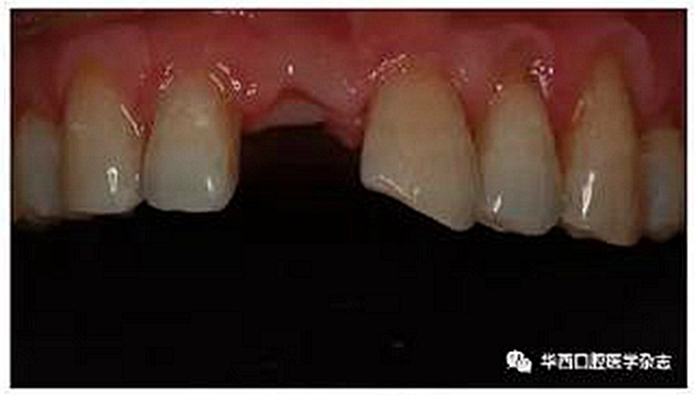

患者因血糖過高無法行種植義齒修復,又拒絕進行局部活動義齒修復,希望在保持美觀的前提下盡量減少對其基牙的預(yù)備,因此選擇單端全瓷樹脂粘接橋修復。粘接橋以左側(cè)上頜中切牙(21牙)為基牙,橋體設(shè)計為改良蓋嵴式。21牙的預(yù)備方式:選擇舌側(cè)開窗型預(yù)備,舌側(cè)釉質(zhì)均勻磨除約0.5 mm,盡量保證牙體預(yù)備在釉質(zhì)范圍內(nèi)完成。21牙鄰面的預(yù)備要求:近中鄰面磨除影響修復體唇舌向就位的倒凹,遠中鄰面在不破壞鄰接區(qū)的前提下盡量向唇側(cè)預(yù)備,呈凹斜面;肩臺為淺凹型,平齊齦緣,寬度約0.3 mm(圖2)。預(yù)備完成后牙面精修拋光,基牙排齦后采用硅橡膠兩層兩次法制取終印模。

圖2 牙體預(yù)備完成后影像